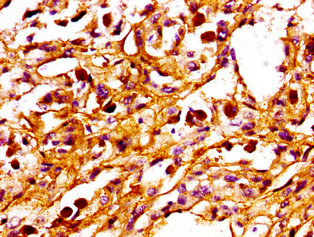

IHC image of CSB-PA018493LA01HU diluted at 1:100 and staining in paraffin-embedded human melanoma performed on a Leica BondTM system. After dewaxing and hydration, antigen retrieval was mediated by high pressure in a citrate buffer (pH 6.0). Section was blocked with 10% normal goat serum 30min at RT. Then primary antibody (1% BSA) was incubated at 4°C overnight. The primary is detected by a biotinylated secondary antibody and visualized using an HRP conjugated SP system.

IHC image of CSB-PA018493LA01HU diluted at 1:100 and staining in paraffin-embedded human pancreatic cancer performed on a Leica BondTM system. After dewaxing and hydration, antigen retrieval was mediated by high pressure in a citrate buffer (pH 6.0). Section was blocked with 10% normal goat serum 30min at RT. Then primary antibody (1% BSA) was incubated at 4°C overnight. The primary is detected by a biotinylated secondary antibody and visualized using an HRP conjugated SP system.